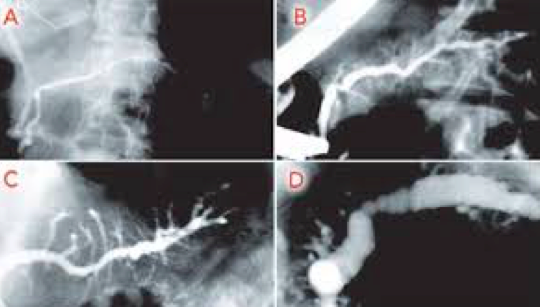

What do you see here?